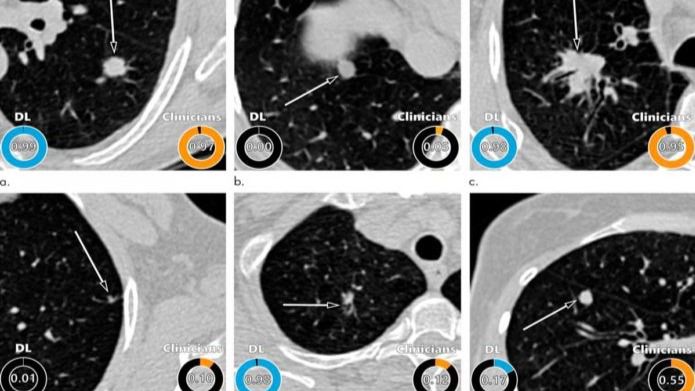

Como explica Kiran Vaidhya Venkadesh en su estudio, que aparece en Radiology, desarrollaron un algoritmo para la evaluación de nódulos pulmonares utilizando el aprendizaje profundo, una aplicación de Inteligencia Artificial capaz de encontrar ciertos patrones en los datos de imágenes.

El algoritmo de aprendizaje profundo arrojó excelentes resultados, superando el modelo Pancanadiense de detección temprana del cáncer de pulmón, establecido para la estimación del riesgo de malignidad de nódulos pulmonares. Su trabajo es comparable al que hubieran llevado a cabo 11 clínicos, incluyendo a especialistas en radiología, oncología y neumología.

Como subraya Kiran Vaidhya Venkadesh, del Grupo de Análisis de Imágenes de Diagnóstico del Centro Médico de la Universidad Radboud, “el algoritmo puede ayudar a los radiólogos a estimar con precisión el riesgo de malignidad de los nódulos pulmonares. Y esto se traduce en optimizar las recomendaciones de seguimiento para los participantes en las pruebas de detección de cáncer de pulmón”.

Por su parte, el profesor Colin Jacobs, miembro de este equipo de la Universidad de Radboud, destaca que al no requerir interpretación manual de las características de las imágenes de los nódulos, “el algoritmo propuesto puede reducir la variabilidad sustancial entre observadores en la interpretación de las imágenes tomadas por TAC. Esto puede dar lugar a menos intervenciones de diagnóstico innecesarias, reducir la carga de trabajo de los radiólogos y disminuir el coste de detección del cáncer de pulmón”.